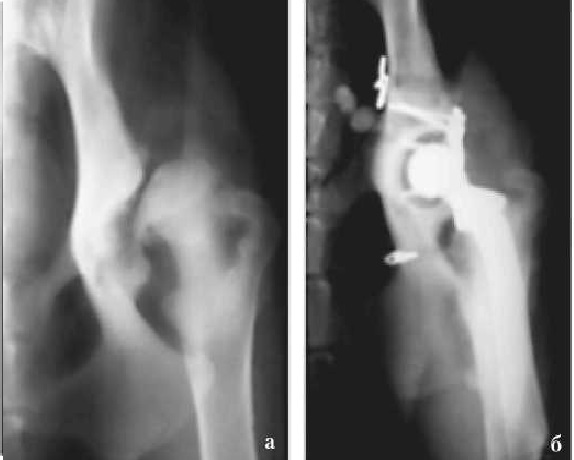

Протезы фирм MATHYS (Швейцария) и AEUSCULAP (Германия) имплантировали 32 собакам обоего пола в возрасте от 8 мес до 2 лет с диагнозом ДТБС.

На первом этапе исследования на 12 собаках (группа 1) отработали технику эндопротезирования и способ фиксации ЭП цементом (в общей сложности выполнено 13 операций).

Четырнадцати собакам, у которых общее число операций по полному эндопротезированию ТБС составило 18 (группа 2), вводили цемент с помощью пистолета-шприца в интрамедуллярный канал с одновременным удалением воздуха через отводящую трубку. Кроме того, у этих животных при соответствующих показаниях проводили костную пластику дорсального края суставной впадины. Для профилактики вывихов в раннем послеоперационном периоде ЭП стабилизировали лавсановой лентой.

Во второй группе животных средний срок службы ЭП составил 1569 сут (от 798 до 2127) (рис. 3). АН развилась в 2 из 18 случаев (11,1 %). Появление хромоты и зоны лизиса костной ткани вокруг цементной мантии ЭП отмечали в среднем через 520 сут (336 и 704). Этим животным операция была выполнена повторно.

Как и в первой группе, отмечен рецидив АН через 147 и 183 сут, в связи с чем пришлось удалять протезы и цементную мантию, а сочленение бедра с тазом выполнять по типу РА. В пяти случаях, чтобы предупредить вывих бедренного компонента ЭП в раннем послеоперационном периоде, использовали следующий прием: в процессе операции стабилизировали сустав лавсановой лентой (периартикулярная стабилизация). Для профилактики вывиха чашки эндопротеза двум животным сделана костная пластика дорсального края суставной впадины (рис. 4).